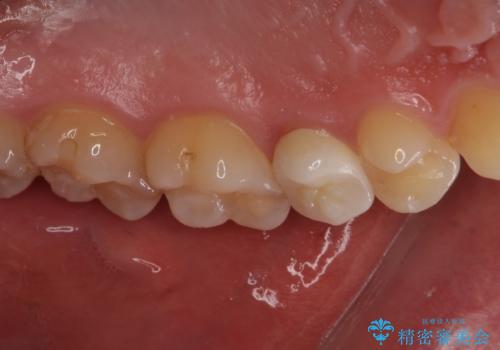

右上もう1本と左上は虫歯治療(セラミックインレー、セラミッククラウン)を行いました。

痛いところがなくなり、患者様には大変満足して頂きました。